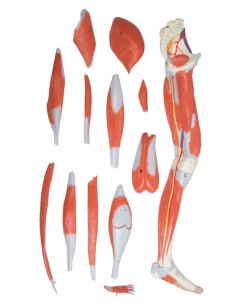

Mini jeu d'articulations avec évidence de la musculature 3B Scientific 1019518